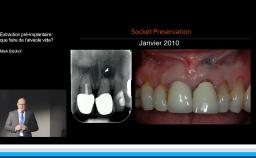

Cette présentation s’intéresse à l’influence des étapes chirurgicales sur le résultat esthétique en implantologie.

Il est communément admis qu’une épaisseur minimale de gencive kératinisée autour des implants est favorable au résultat esthétique mais aussi au maintien d’une bonne santé des tissus péri-implantaires au long terme, mais il n’existe pas de consensus à ce niveau. Une épaisseur osseuse de 2 mm autour des implants est nécessaire pour prévenir les résorptions osseuses et pour soutenir de façon pérenne les tissus mous.

Le moment de l’implantation (immédiate, précoce, différée) influe peu sur le résultat esthétique ; l’implantation immédiate ne supprime pas la résorption physiologique post-extractionnelle.

Tous les types d’implants peuvent être utilisés en secteur antérieur, mais l’utilisation de connexions au niveau osseux offre plus de latitude sur le placement de l’implant et sur la réhabilitation prothétique. Afin de limiter les proximités entre implants et entre dents et implants, l’utilisation d’implants de faible diamètre et la réduction du nombre d’implants sont des options à considérer.